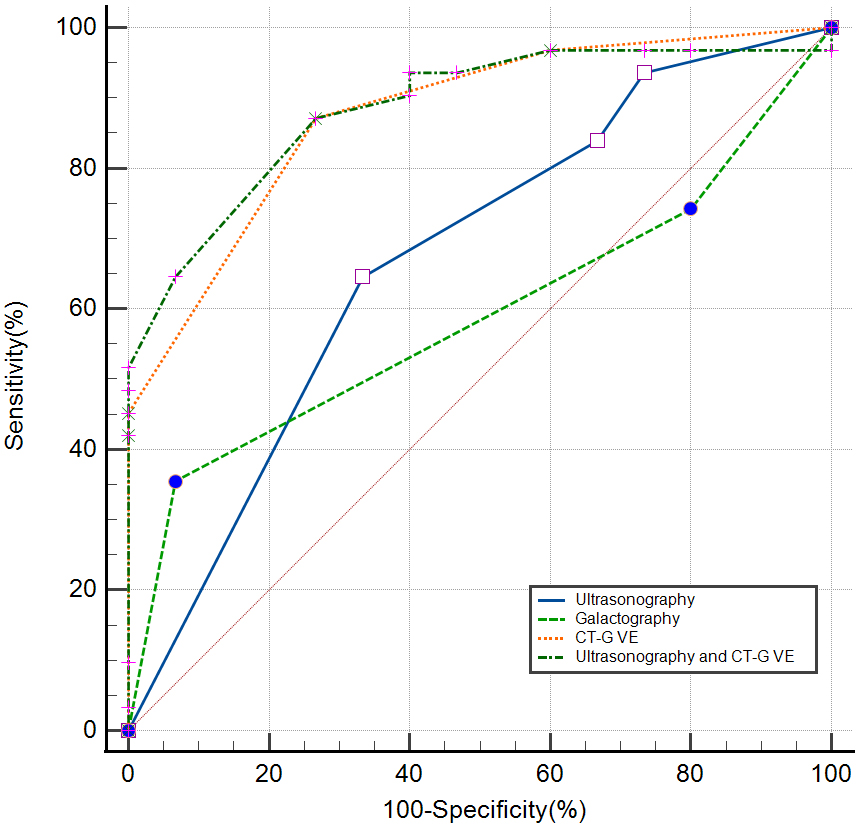

ROC curve analysis (Tables 3,4 and Fig. 5) was performed for ultrasonography, galactography, and CT-G VE to evaluate the diagnostic performance of all three imaging modalities for PND diseases. The sensitivity for identifying high-risk and malignant lesions in PND was 64.52% [95% confidence interval (CI) 45.40–80.90%] for ultrasonography, 35.48% (95% CI 19.20–54.60%) for galactography, 87.10% (95% CI 70.20–96.40%) for CT-G VE, and 87.10% (95% CI 70.20–96.40%) for CT-G VE combined with ultrasonography. The specificity for identifying high-risk and malignant lesions in PND was 66.67% (95% CI 38.40–88.20%) for ultrasonography, 93.33% (95% CI 68.10–99.80%) for galactography, 73.33% (95% CI 44.90–92.20%) for CT-G VE, and 73.33% (95% CI 44.90–92.20%) for CT-G VE combined with ultrasonography. The AUC was 0.672 for ultrasonography, 0.588 for galactography, 0.876 for CT-G VE, and 0.885 for CT-G VE combined with ultrasonography. The detection ability of CT-G VE for high-risk and malignant lesions was higher than that of ultrasonography (p = 0.0056) and galactography (p = 0.0008). However, there was no significant difference between the detection abilities of ultrasonography and galactography (p = 0.4780). The detection abilities of CT-G VE alone and CT-G VE combined with ultrasonography were comparable (p = 0.6412). The cut-off point was the polypoid-solitary type for CT-G VE, category 3 for ultrasonography, and grade Ⅱ for galactography.

| Imaging modality | Cut-off point | Sensitivity% | Specificity% | AUC | p |

|---|---|---|---|---|---|

| (95% CI) | (95% CI) | (95% CI) | |||

| Ultrasonography | 3 | 64.52 (45.40–80.90) | 66.67 (38.40–88.20) | 0.672 (0.518–0.803) | 0.0360 |

| Galactography | II | 35.48 (19.20–54.60) | 93.33 (68.10–99.80) | 0.588 (0.433–0.731) | 0.2461 |

| CT-G VE | Polypoid-solitary type | 87.10 (70.20–96.40) | 73.33 (44.90–92.20) | 0.876 (0.746–0.955) | |

| CT-G VE combined with Ultrasonography | 87.10 (70.20–96.40) | 73.33 (44.90–92.20) | 0.885 (0.756–0.960) |

Abbreviations: ROC, Receiver operating characteristic; CT-G VE, Computed tomography-galactography virtual endoscopy; AUC, Area under the curve; CI, Confidence interval.

| Imaging modality | Difference in AUC | Z | p |

|---|---|---|---|

| Ultrasonography vs. galactography | 0.0839 | 0.710 | 0.4780 |

| CT-G VE vs. ultrasonography | 0.204 | 2.772 | 0.0056 |

| CT-G VE vs. galactography | 0.288 | 3.345 | 0.0008 |

| CT-G VE combined with ultrasonography vs. CT-G VE | 0.00860 | 0.466 | 0.6412 |

Abbreviations: AUC, Area under the curve; CT-G VE, Computed tomography-galactography virtual endoscopy.

Fig. 5.

Fig. 5.Receiver operating characteristic (ROC) curves for the diagnostic performance of ultrasonography, galactography, computed tomography-galactography virtual endoscopy (CT-G VE), and CT-G VE combined with ultrasonography.